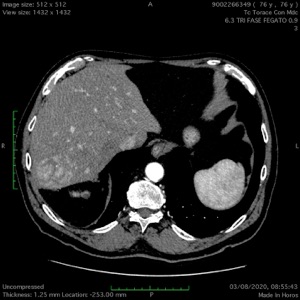

HCC 7 SEGMENTO RECIDIVO: ABLAZIONE MEDIANTE MICROONDE CONGUIDA ECG E CEIOUS

Pz di 77 anni con recidiva locale di HCC in 7s già pluritrattato nella stessa sede con termoablazioni percutanee (5 sessioni). Non resecabile in quanto la recidiva voluminosa (50mm) prende contatto con la sovraepatica dx: il pz non ha i criteri adeguati per una epatectomia dx